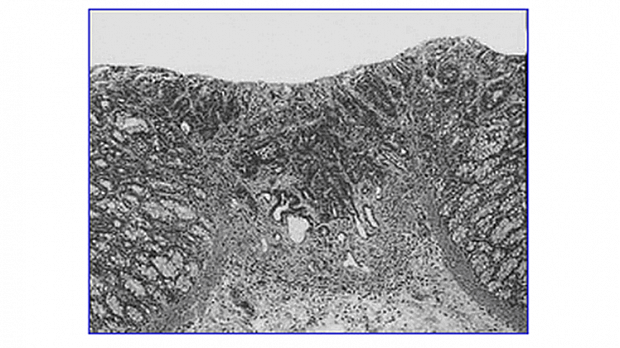

Отсевы это изолированные клетки опухоли или группы клеток расположенные в других отношениях здоровых тканях (рис. 4).

Отсевы могут рассматриваться в качестве начальной формы инвазии, предшествующей сосудистой инвазии. Она является независимым фактором риска поражения лимфатических узлов не только при раннем, но и распространенном КРР [12, 14].